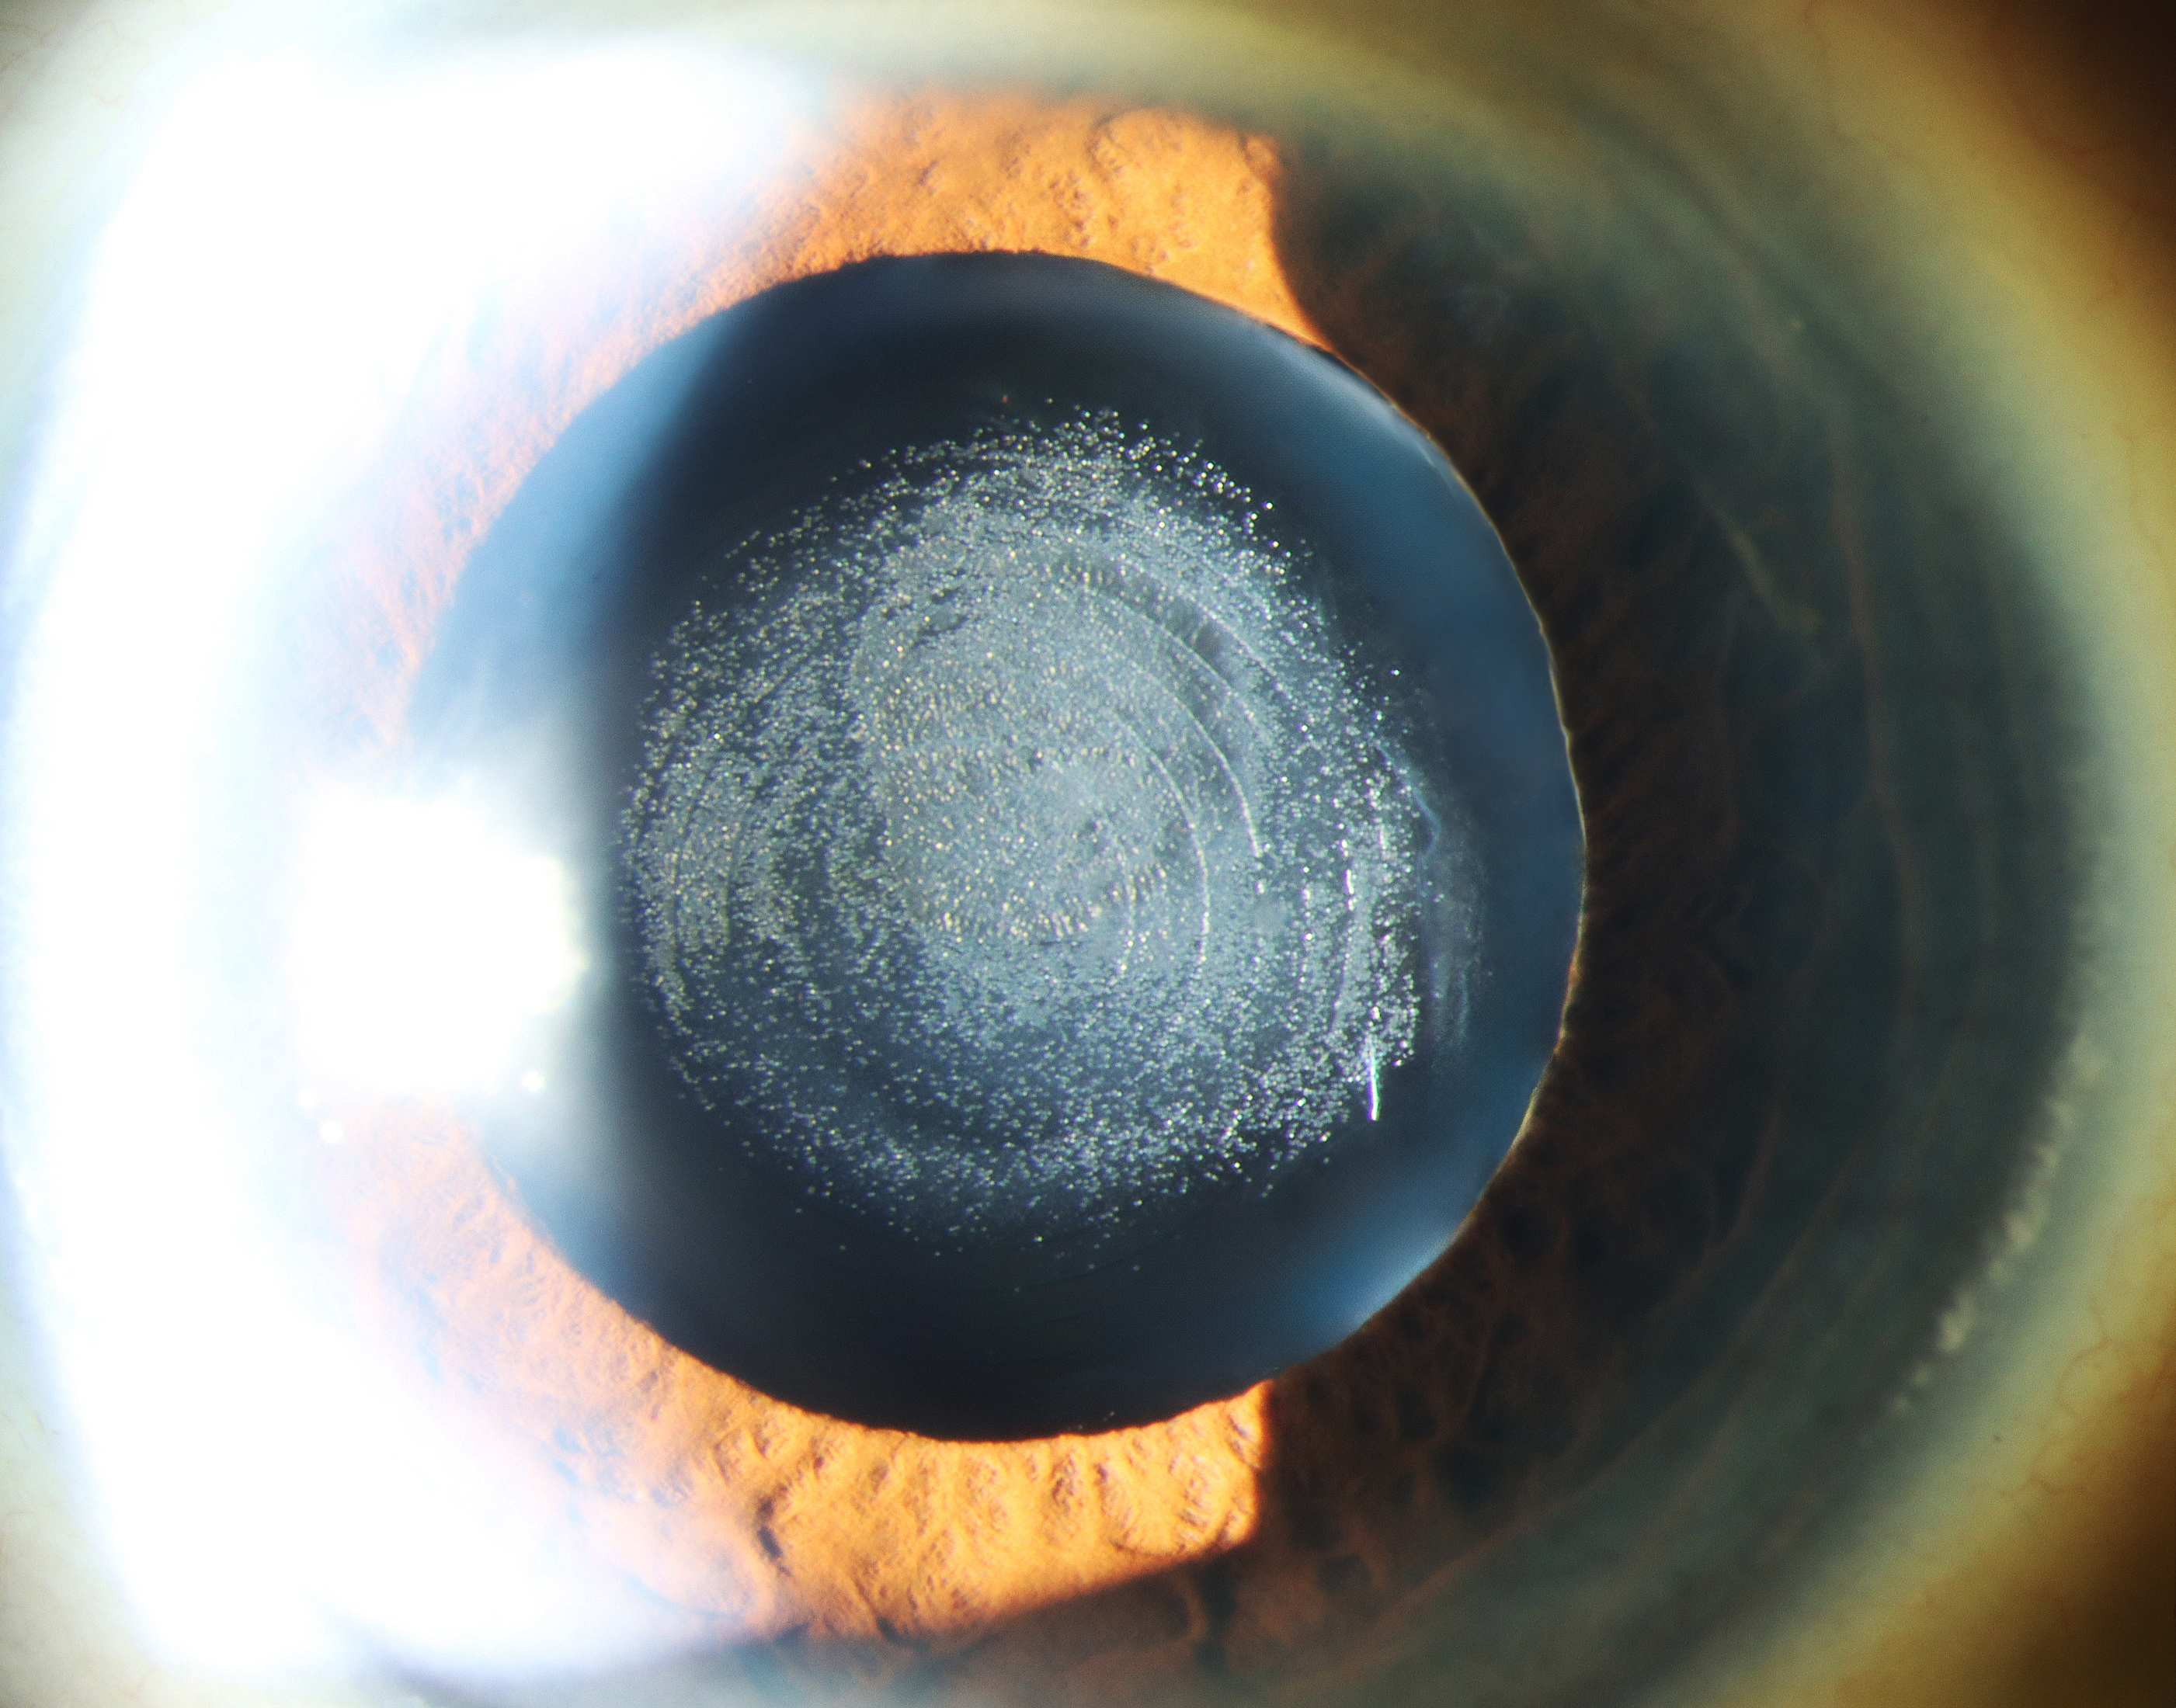

Ruptured Capsule Presented by Alexandra Copple, CRA This photograph received Second Place, Slit Lamp in the 2025 OPS Scientific Exhibit. Filed Under Retina OPS Photo